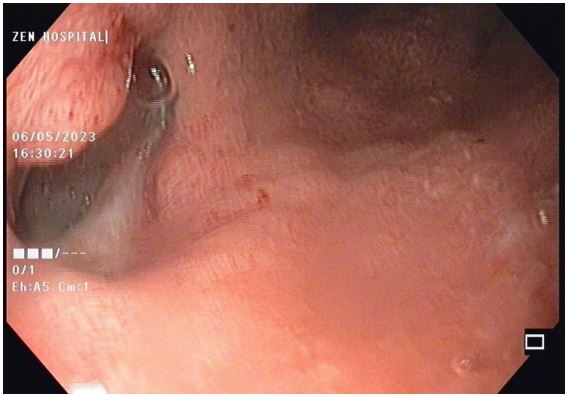

A UGI endoscopy performed to prepare for the endovac revealed a partial breakdown of the anastomosis with a defect size of 3 cm and a subdiaphragmatic cavity filled with slough. The cavity was entered with a scope, and de-sloughing was accomplished with a brush. Normal saline was used to irrigate the cavity. Endovac was used. Forty-eight hours after beginning endovac therapy, there was a significant decrease in SIRS response as measured by fever, pulse rate, WBC count, and CRP. Endovac was done twice more at 5-day intervals. The therapy lasted two weeks in total. At each endoscopic session, the size of the sponge used was reduced, and the cavity size and amount of slough were significantly improved (Figure 7). After 2 weeks of endovac therapy, a CT oral contrast study revealed a significant reduction in cavity size with a well-formed fistula that closed in about 8 weeks. Endoscopies were performed at 3 and 6 months. Both were normal, and the patient is currently on a complete oral diet.

Figure 7: Healed anastamotic leak of stomach after E vac therapy.